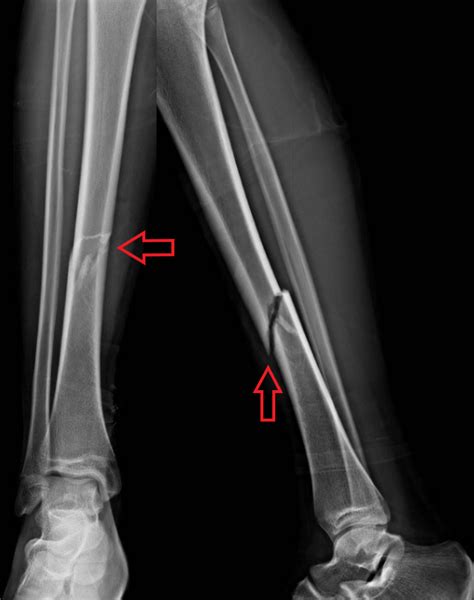

Správna diagnostika je kľúčová. Čím lepší diagnostický prístroj použijeme, tým lepšie sa veterinár dokáže orientovať v priestore postihnutej lokácie a je vďaka tomu schopný navrhnúť ideálny postup pri riešení zlomeniny. Na diagnostiku zlomenín sa používa RTG, CT (počítačová tomografia) a pri úrazoch chrbtice alebo lebky aj MRI. Vo vybavení moderných veterinárnych kliník nájdete najvyspelejšie CT a MRI prístroje, ktoré sa používajú štandardne v humánnej medicíne a poskytujú oveľa lepšie diagnostické výsledky.

Forma liečby je priamo závislá od typu fraktúry, ktorú určí po detailnej diagnostike veterinár. Konzervatívne riešenie: niektoré zlomeniny (nie je ich bohužiaľ veľa), zvlášť u veľmi mladých jedincov, môžu byť našťastie liečené bez nutnosti operácie. Pre väčšinu pacientov je ale pre dosiahnutie dobrého výsledku najlepšou možnosťou operácia. Zásadný rozdiel pri liečbe zlomenín u malých zvierat a človeka je v tom, že sa nemôžeme spoľahnúť na kľudový režim, ktorý je nutný pre dobré zhojenie zlomeniny.

Chirurgické riešenie: použitie bandáží a iných, v humánnej medicíne bežných variantov, môže vyústiť vo veľmi vážne komplikácie pacienta (poškodenie svalov, nervov a stuhnutosť kĺbov), preto je od tejto metódy stabilizácie upúšťané, a veterinár volí skôr operačné riešenie. Zvlášť u končatín operácia umožní, aby bola zlomená kosť navrátená do pôvodnej polohy a stabilizovaná. Pri týchto operáciách sa využívajú na stabilizáciu kostí dlahy a skrutky, alebo zevné fixačné aparáty. Vďaka fixácii je väčšina pacientov po operácii v psychickej pohode a sú schopní dokonca končatinu znovu používať k normálnej chôdzi. Na záver operačnej starostlivosti je pri ďalšom operačnom zákroku fixačný materiál vyňatý z tela pacienta a kosť sa po spojení začne hojiť.

Typ starostlivosti o pacienta so zlomeninou je rôzny podľa typu zlomeniny. Typ starostlivosti určí veterinár po liečebnom zákroku. Väčšina pacientov má obmedzený pohyb, najmä je potrebné zamedziť zvieraťu v behaní a skákaní. V dobe, keď nie je pacient pod dohľadom, je nutné ho umiestniť do obmedzeného priestoru - predsieň, klietka, kotec atp. Občas je potrebné pridať na krk golier, aby si pacient nechcel strhnúť obväzy a pod. Vo väčšine prípadov zhotovujeme po 6-8 týždňoch kontrolné diagnostické snímky (RTG, CT, MRI), ktoré veterinárom zodpovedia, či je kosť dostatočne zahojená. Obvykle nie je potrebná ďalšia liečba či obmedzenie a pacient sa môže pohybovať úplne bežne. V prípade zachovania správnej pooperačnej starostlivosti a dobrej prognózy, je výhľad pacienta veľmi dobrý. Väčšina operačne liečených pacientov získava opätovnú excelentnú funkčnosť ako u zdravej končatiny a s tým aj dobrú kvalitu života. Hojenie tiež ovplyvňuje vek pacienta, prítomnosť prípadnej osteoartrózy a predovšetkým priebeh pooperačnej starostlivosti. Dôležitou a vhodnou súčasťou pooperačnej starostlivosti je fyzioterapia. Na niektorých klinikách majú k dispozícii rehabilitačné stredisko s hydroterapiou.